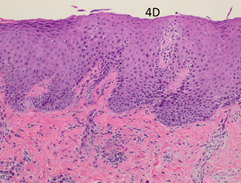

Figure 4D Biopsy taken from the recurrent infield RT area (position A in Figure 3F). Post RT x 100showing that the psoriasiform hyperplasia and inflammation are less marked in this recurrent plaque. The papillary dermal vessels are not as plump, and no neutrophil aggregates are present in the epidermis.

The post-RT biopsy of the clinically recurrent psoriasis is seen in Figure 4D. This shows the histopathology of the recurrent lesion at eight weeks. The findings of psoriasis are present to a lesser degree than in the pre-RT biopsy. The post-RT biopsy of the clinically normal skin is seen in Figure 4E and shows essentially normal skin whereas, prior to RT, there was florid psoriasis.